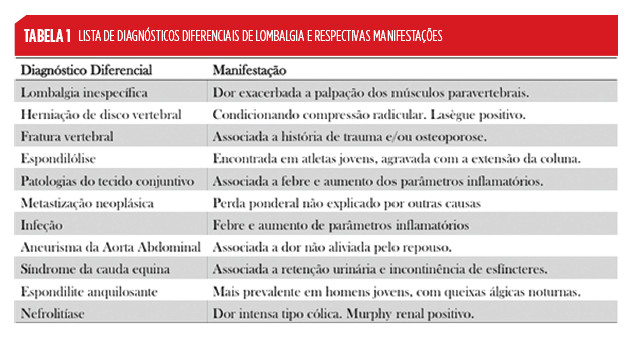

A lista de diagnósticos diferenciais é extensa, apresentando alguns diagnósticos especificidades relevantes.

Devida à extensa lista de diagnósticos diferenciais, foram criadas red flags (Tabela 2), cuja presença durante a história clínica e/ou exame objetivo, implica um estudo etiológico mais aprofundado.